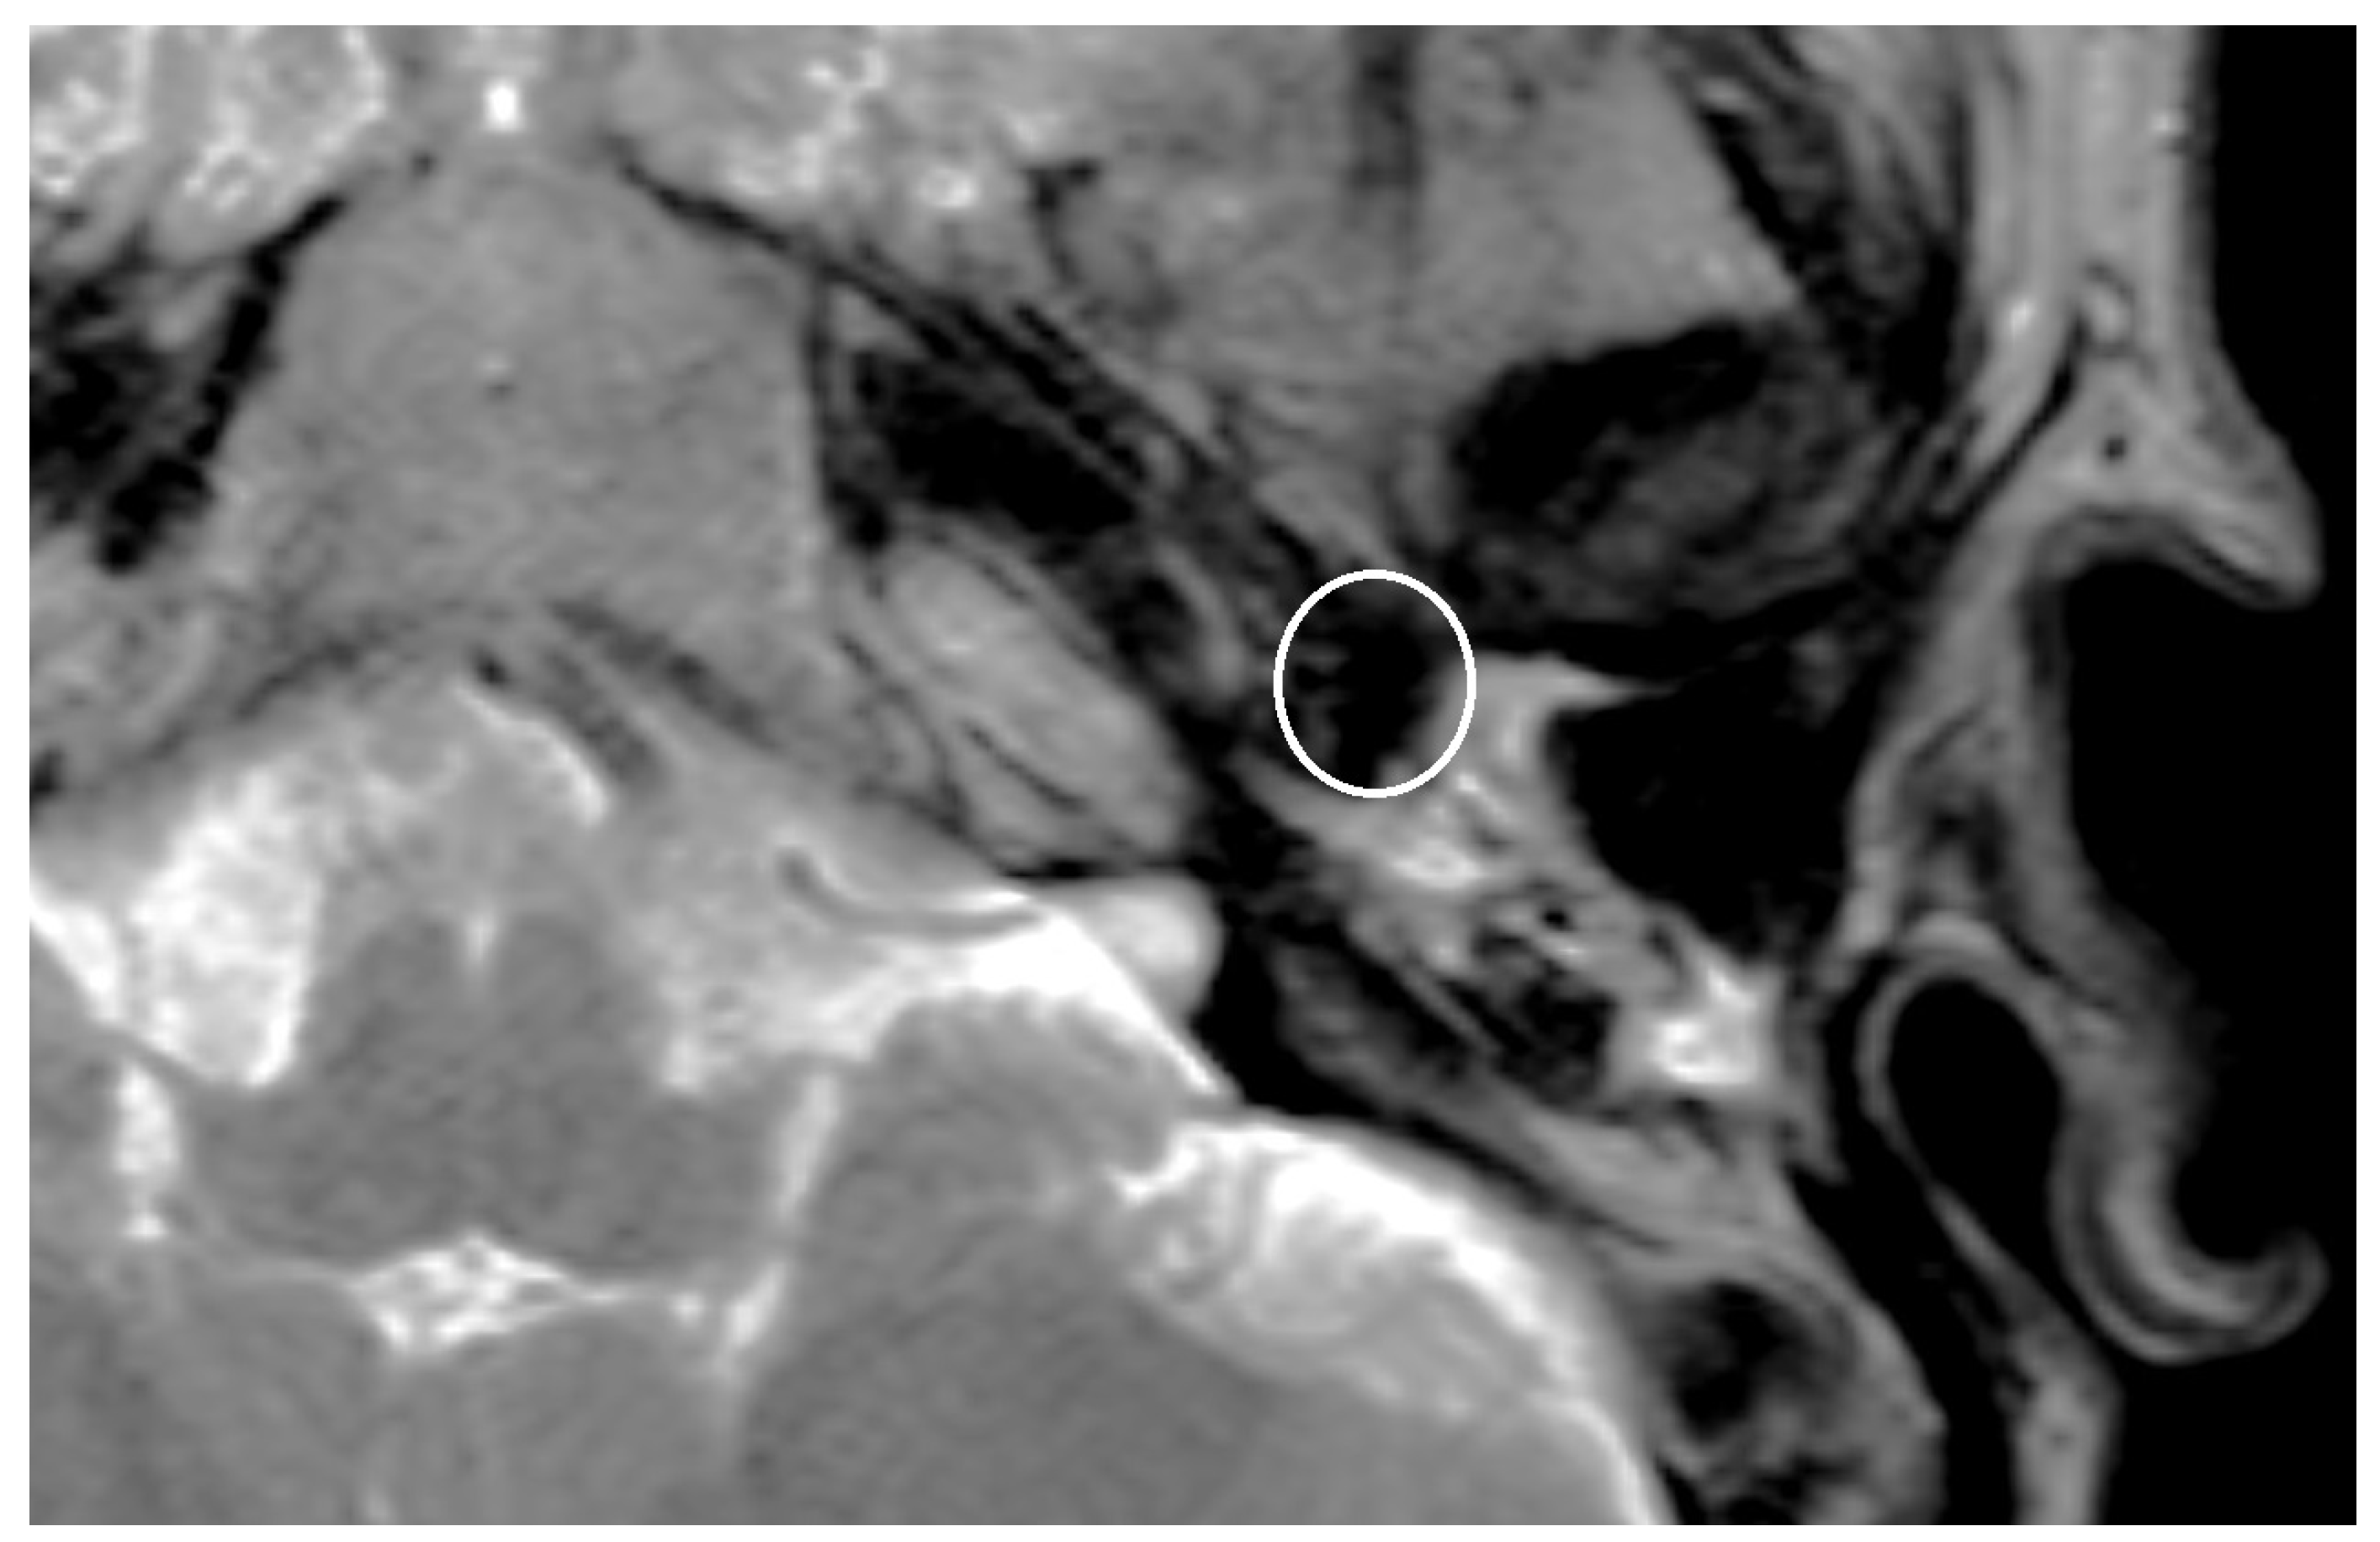

| Size of artifact | 3.60 (sd = 1.01, min = 2.50, max = 4.50) | 3.11 (sd = 0.54, min = 2.20, max = 4.50) | 4.74 (sd = 0.77, min = 3.90, max = 6.10) |

| PORP | 2.0 mm | 3.1 mm | 5.4 mm |

| TORP | 3.6 mm | 4.7 mm | 7.2 mm |

| Mesh | 0.1 mm | 3.6 mm | 5.8 mm |